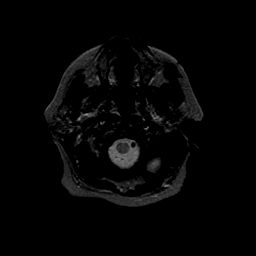

Basal Ganglia Calcification: T2-weighted MR -- Slice #1

[Home][Help][Clinical] Slice 1